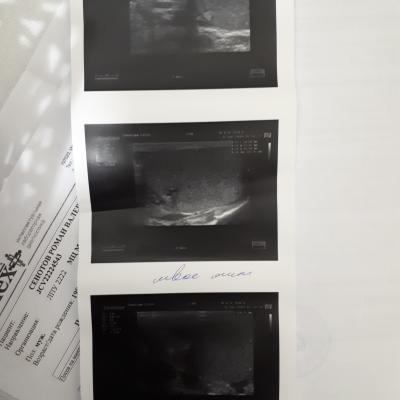

Здравствуйте ! месяц назад почувствовал резкую боль в правом боку, было подозрение на аппендицит (не подтвердилось) вместе с этой болью заболело правое яичко. Обратился к врачу сделал обследование пролечился не помогло боли остались. Обратился к другому урологу, он провел обследование назначил лечение. Вопрос правильный ли диагноз и назначенное лечение? (все обследования на фото)

Здравствуйте! Очень грамотное, сбалансированное лечение. Поздравляю с отличным доктором! Удачи!